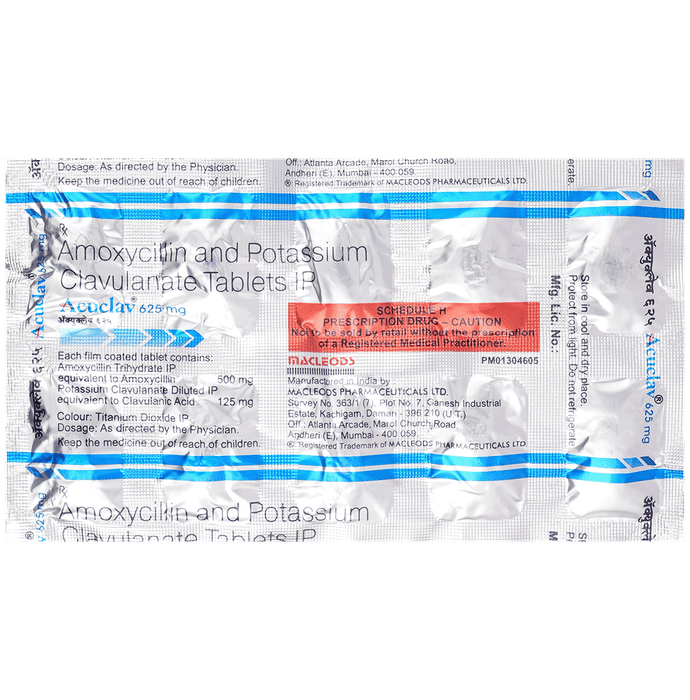

Prescription Required:Macleods Pharmaceuticals Pvt Ltd:<medicine_type>:

Amoxycillin (500mg) + Clavulanic Acid (125mg):<packagingdetail>:Strip:

10:<productform>::Store below 30°C:

Macleods Pharmaceuticals Pvt Ltd | Atlanta Arcade, Marol Church Road, Andheri (East), Mumbai – 400059, INDIA.::